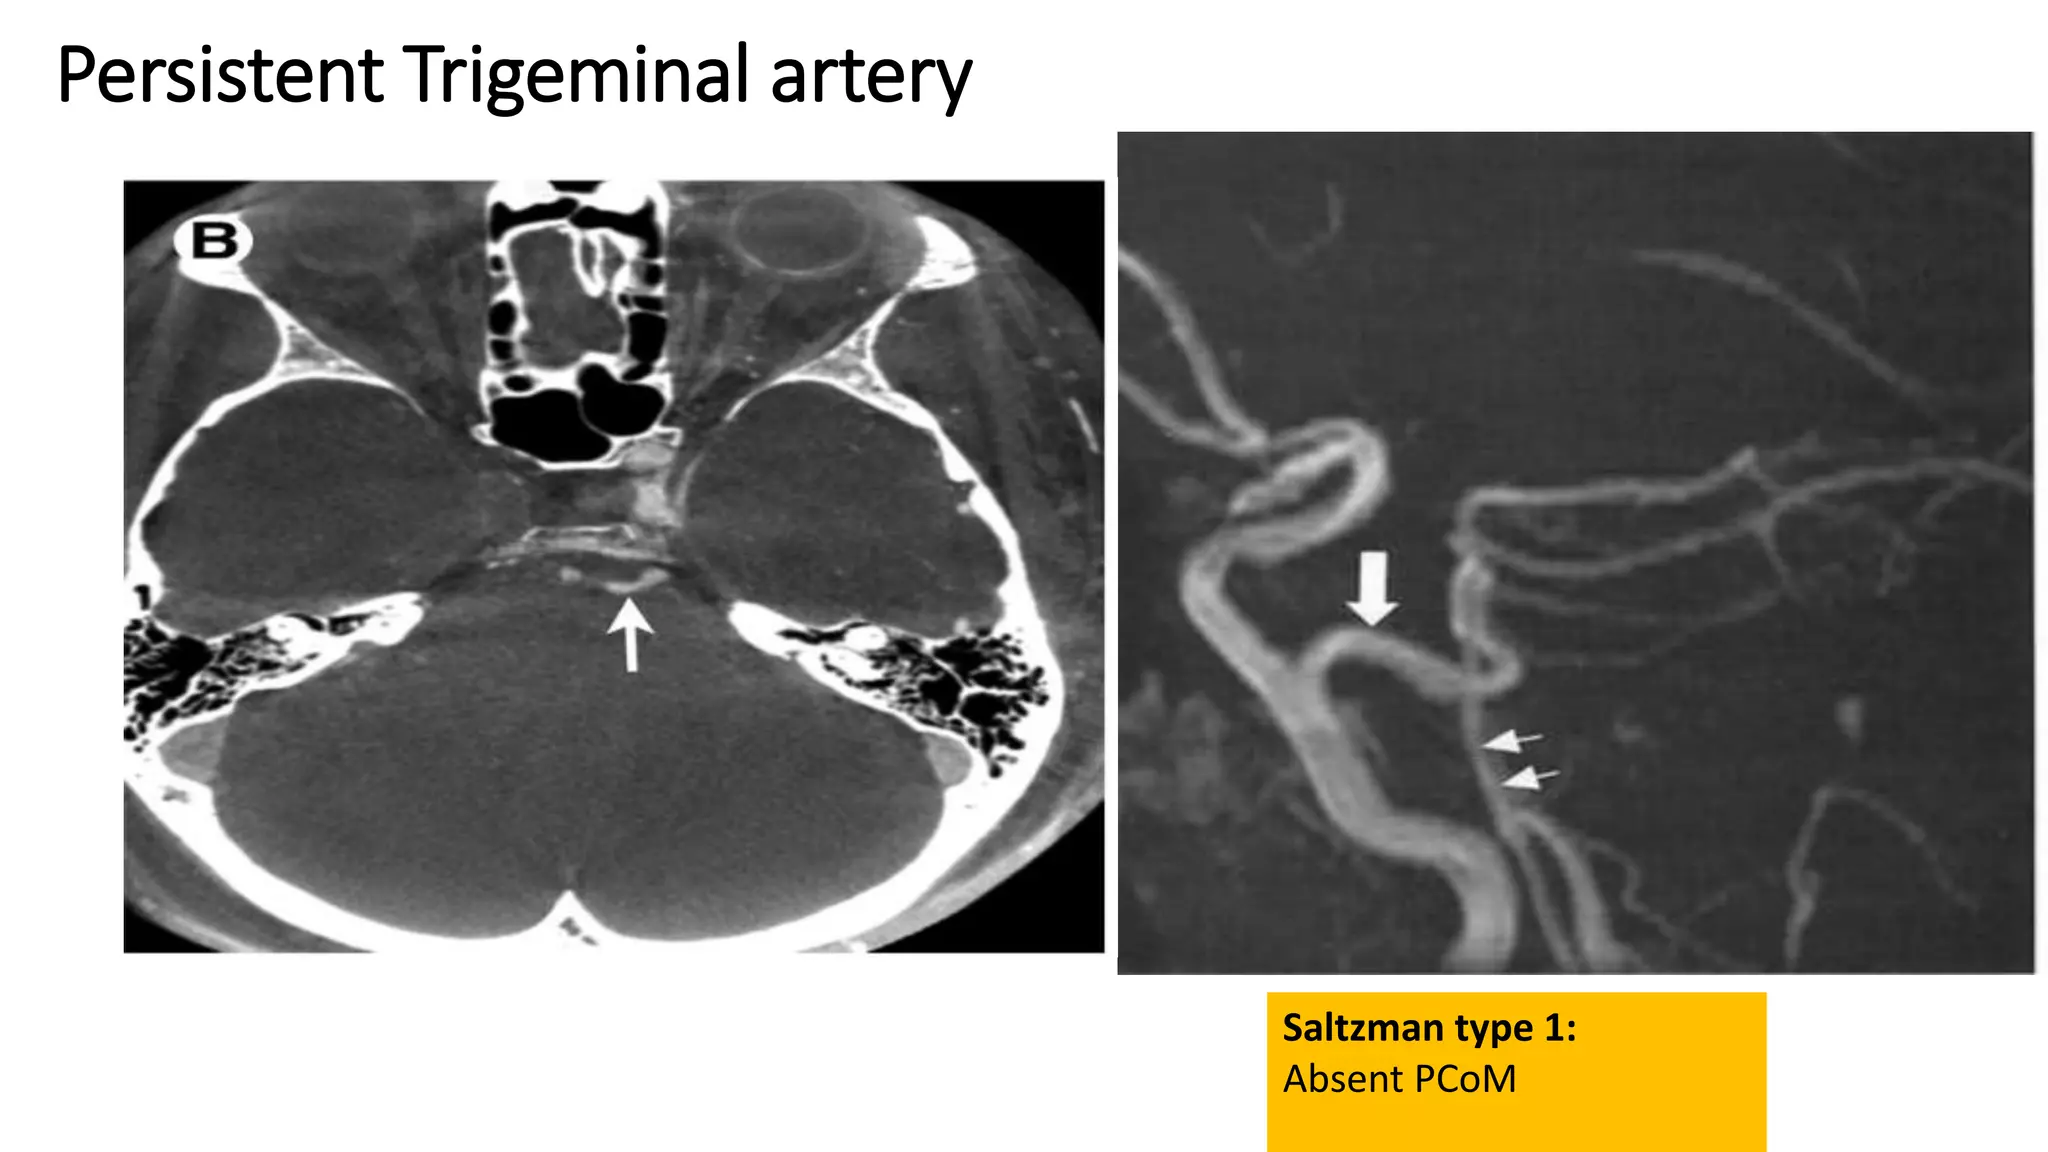

Persistent trigeminal artery:

• Most common of the persistent

embryonic carotid-basilar anastomose

• Identified in 0.1-0.2%

• PTA arises from posterior genu of

cavernous segment of ICA

Persistent trigeminal artery

Saltzmann type I:

• PTA joins the basilar artery between the superior cerebellar arteries and

anterior inferior cerebellar arteries.

• The basilar artery proximal to the junction is usually hypoplastic

• PCoAs are absent

• PTA supplies the entire vertebrobasilar system distal to the anastomosis.

Saltzmann type II:

similar to type 1 but PCoAs are present and supply the posterior cerebral

arteries

Saltzmann type III :

which directly joins to the cerebellar artery.

Saltzman type 1:

Absent PCoM